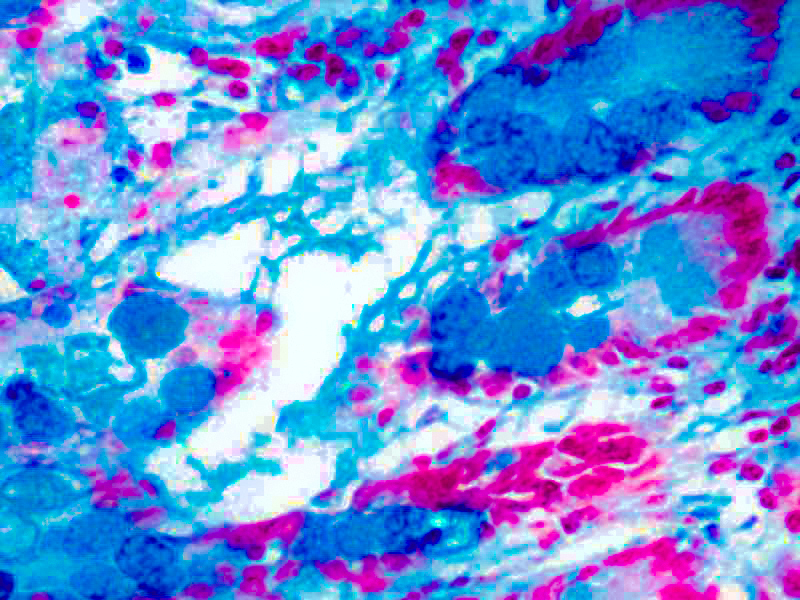

This kit stains strongly sulfated mucosubstances. Strongly sulfated mucosub-stances stain blue in paraffin tissue sections, while the nuclei stain pink to red and the cytoplasm and background stain pale pink.